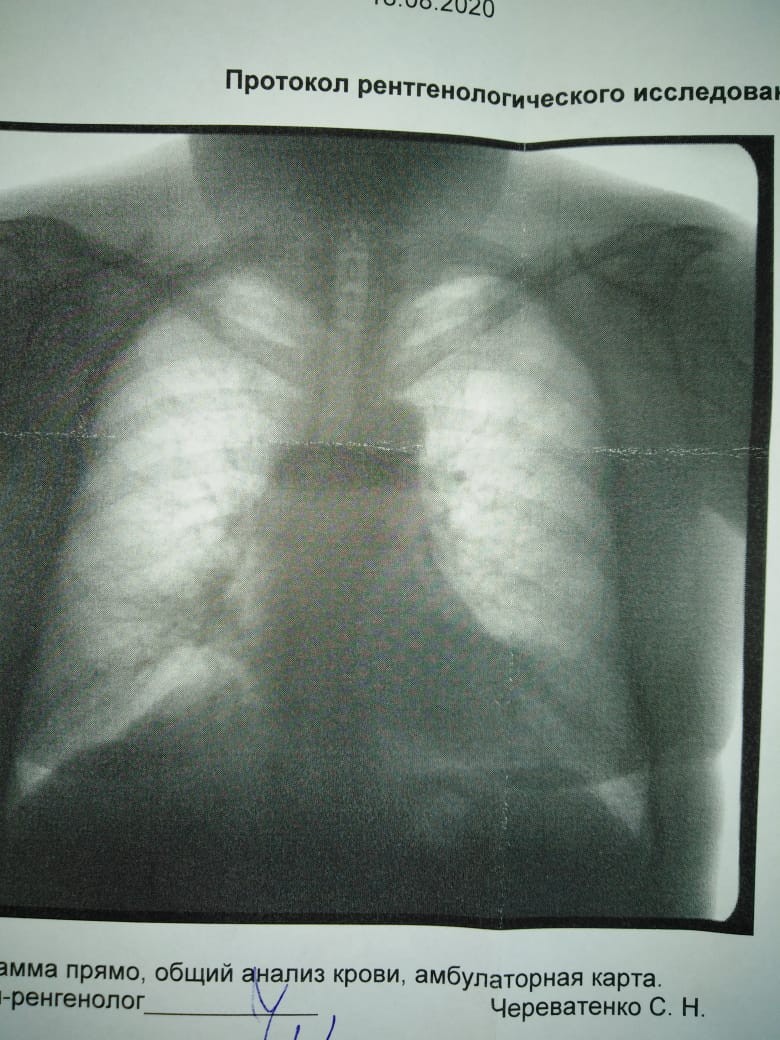

Фотографии рентгеновских снимков без необходимости направления от врача